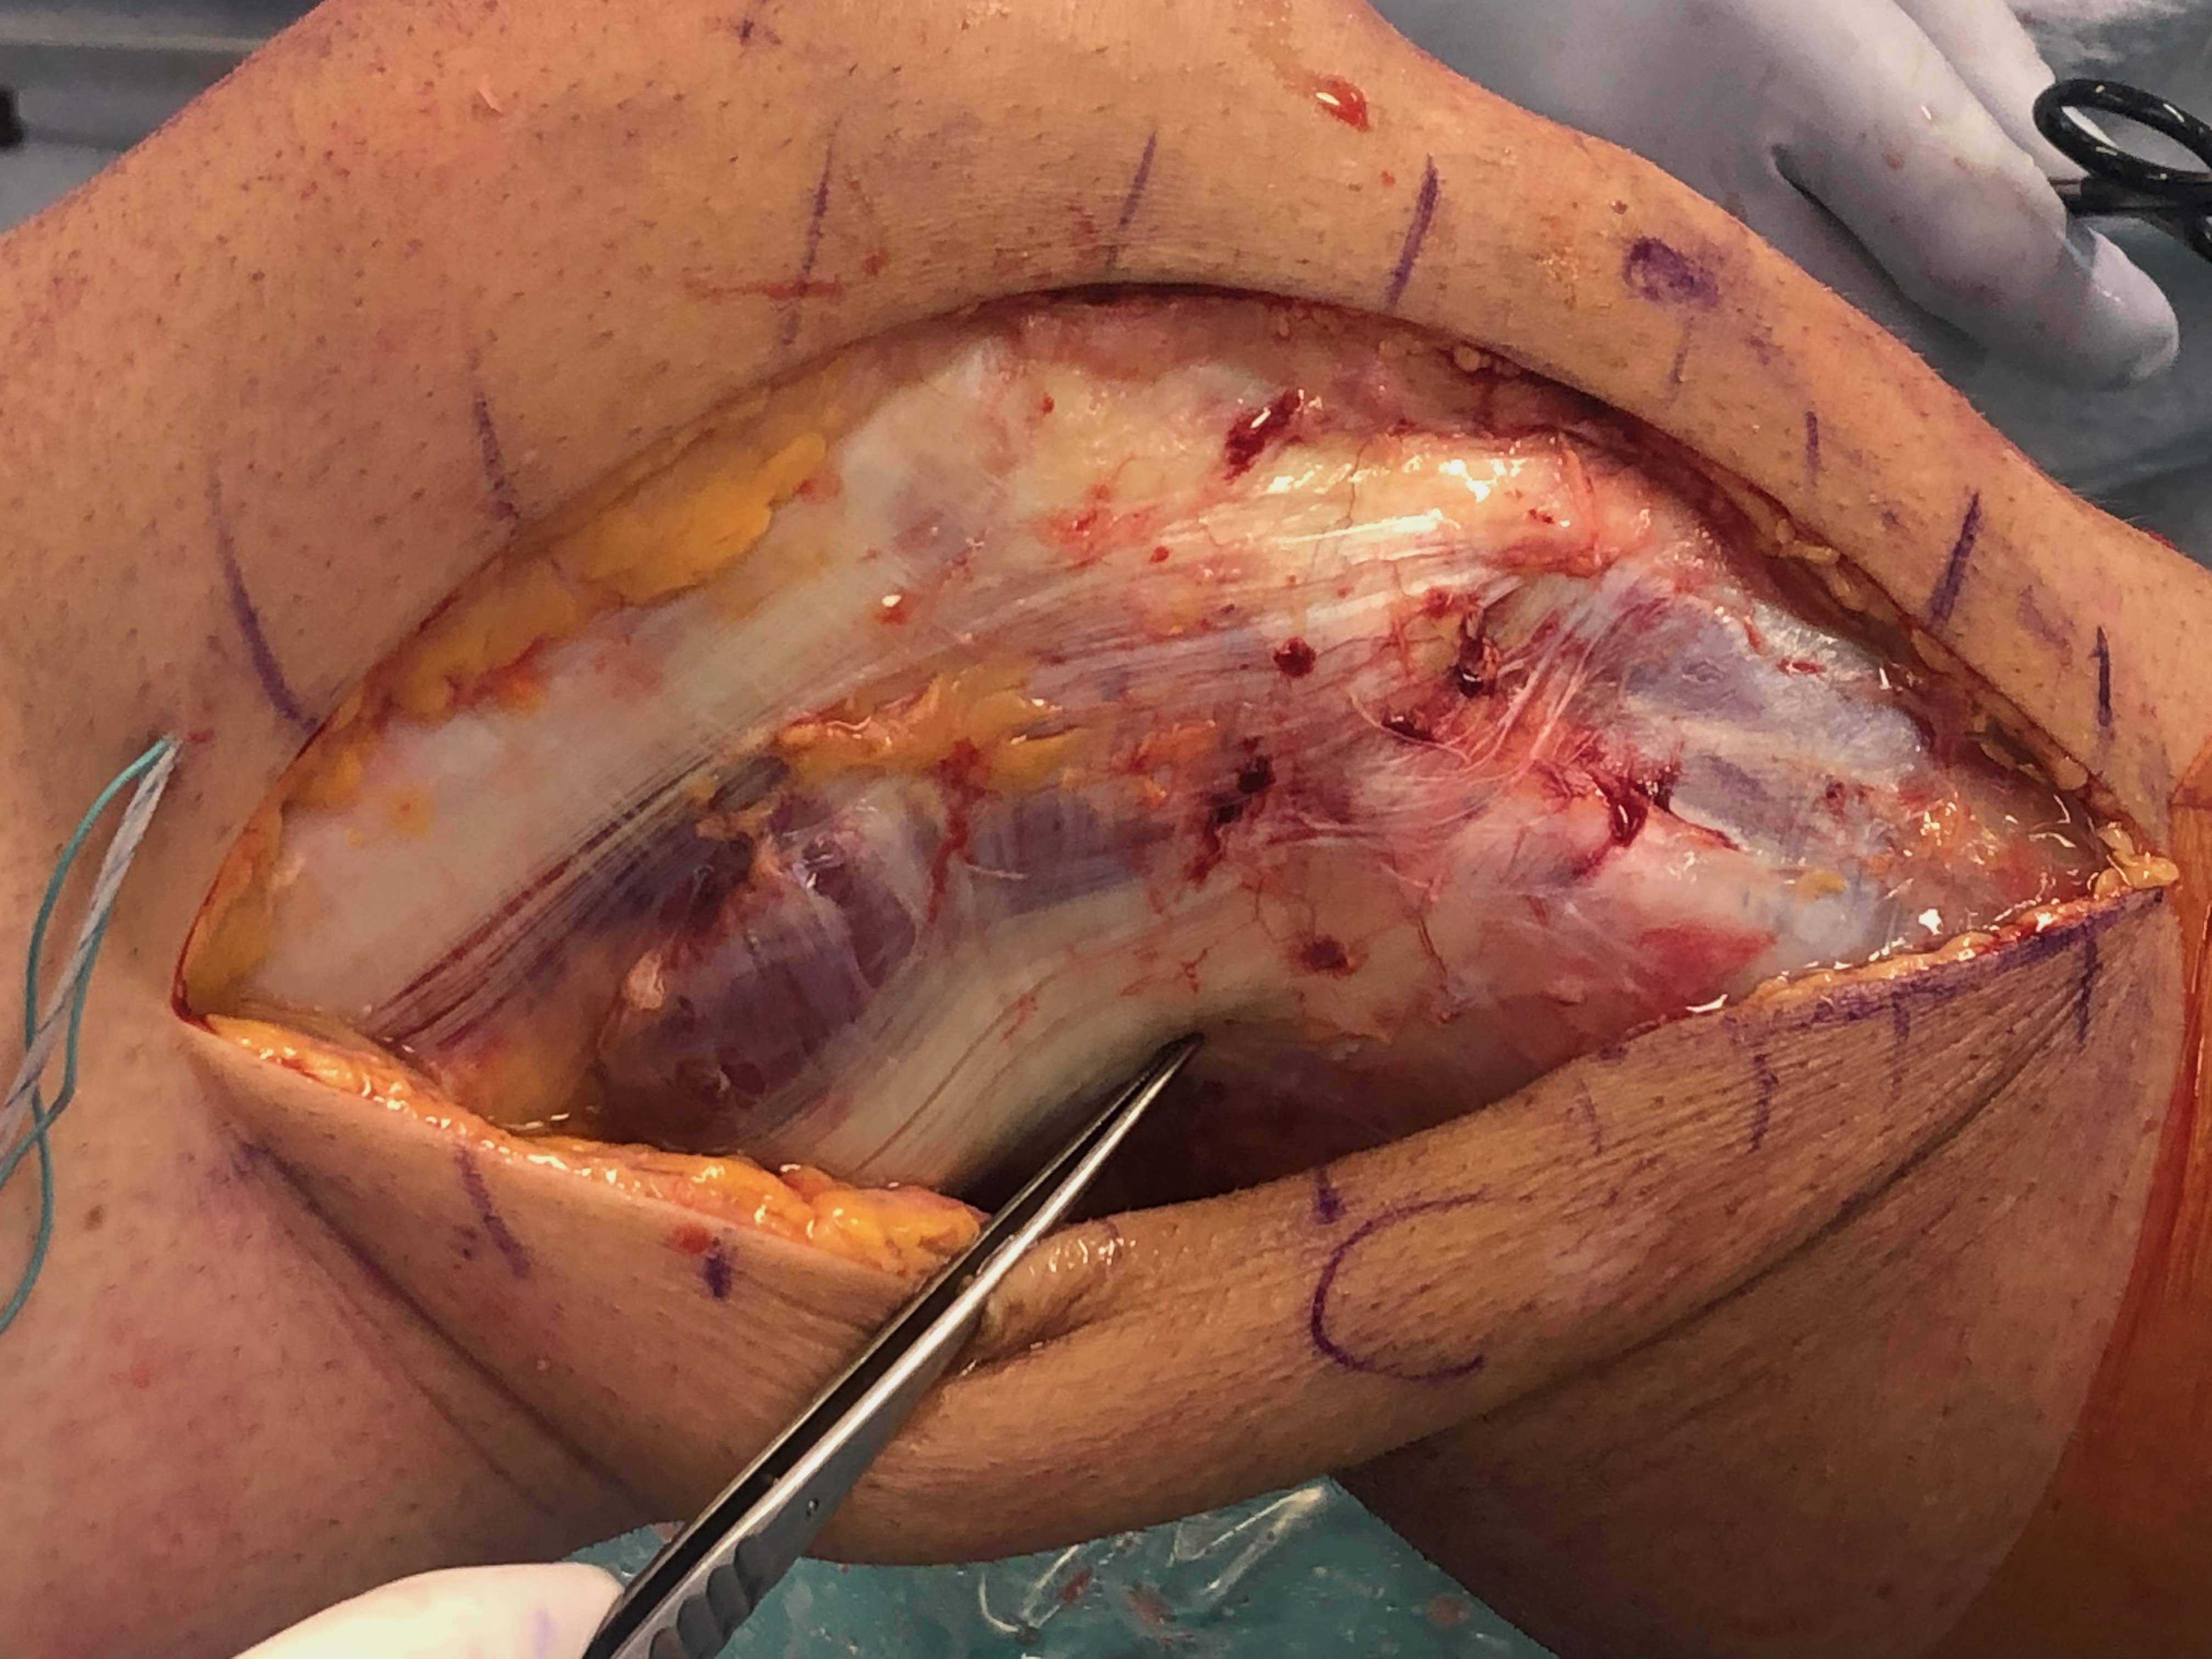

Left knee with LCL and popliteus tunnels and screw fixation of grafts